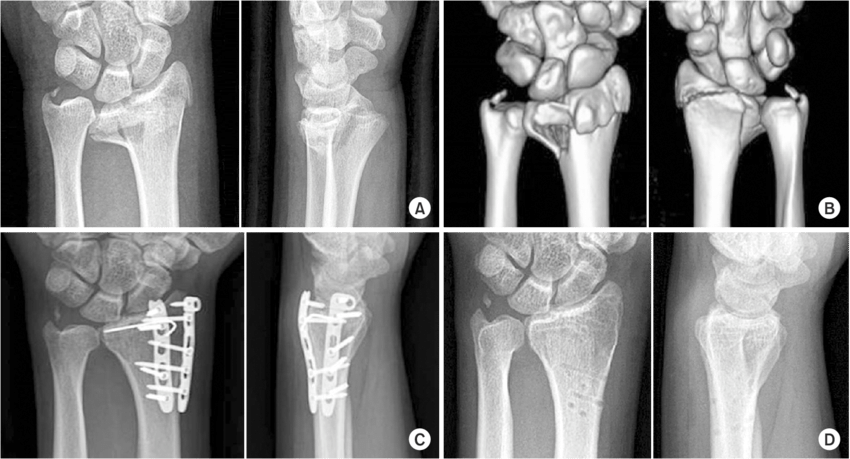

Radiografías: Son la herramienta principal para visualizar las fracturas de muñeca.

Tomografía Computarizada (TC): Puede proporcionar imágenes más detalladas si la radiografía no es concluyente.

Cuando las fracturas son complejas o están desplazadas, puede ser necesaria la cirugía:

Reducción Abierta y Fijación Interna (ORIF): Este procedimiento implica la colocación de placas y tornillos para mantener los huesos en su lugar.

Fijación Externa: Se utilizan pines y una estructura externa para mantener los huesos en su lugar.